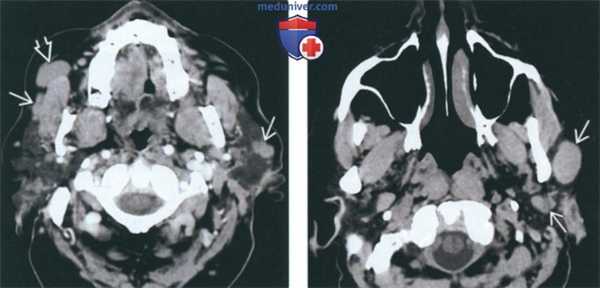

(Слева) КТ с КУ. Визуализируются множественные двусторонние округлые опухоли Вартина, плохо накапливающие контраст. Обратите внимание, что справа опухоль захватывает добавочную долю околоушной железы.

(Справа) КТ без КУ, аксиальная проекция. Наблюдаются множественные округлые опухоли Вартина. Контуры опухолей четкие, размеры варьируют. В 20% случаев заболевание носит множественную форму. Новообразования могут возникать как в одной, так и в обеих железах.в) Дифференциальная диагностика опухоли Вартина:

(Слева) На аксиальной КТ с КУ в околоушных железах определяются множественные двухсторонние опухоли Уортина овоидной формы, плохо накапливающие контраст. Обратите особенное внимание на опухоль в добавочной доле околоушной железы.

(Справа) На аксиальной КТ без КУ в левой околоушной железе визуализируются множественные овоидные, хорошо отграниченные опухоли Уортина различного размера. У 20% пациентов опухоли Уортина множественные (множественные очаги в одной железе или в обеих).в) Дифференциальная диагностика опухоли Уортина: